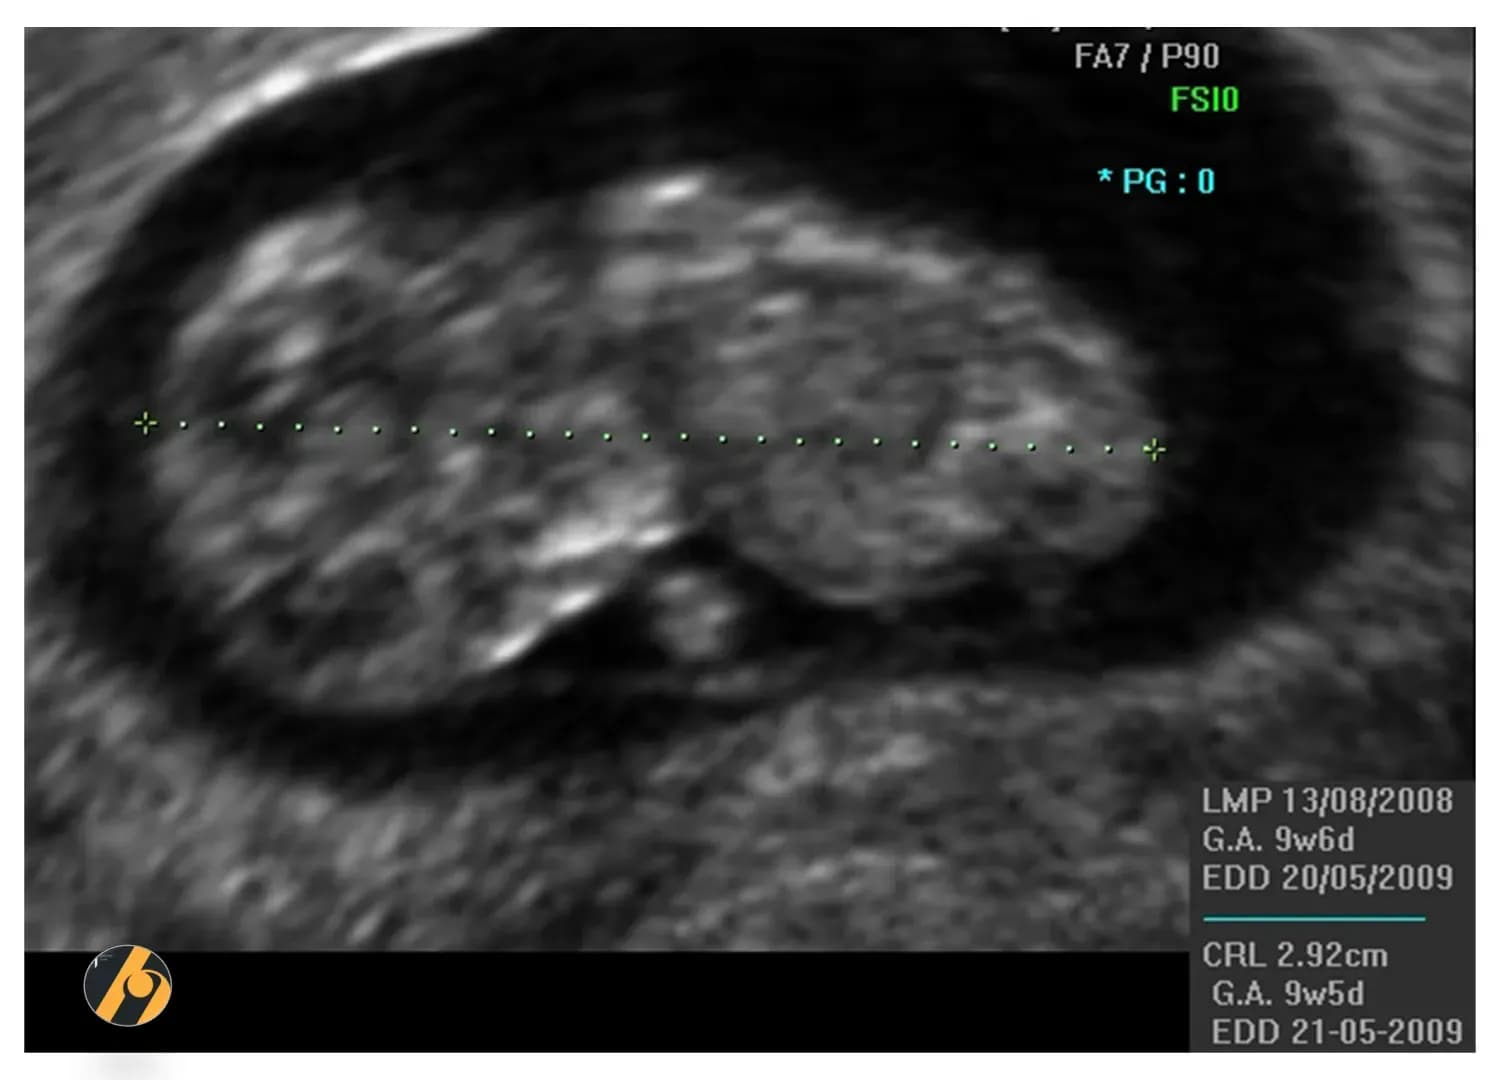

Fetus je dug oko 3–4 cm i teži oko 4–5 g. Prsti na rukama i nogama su potpuno odvojeni, razvijaju se nokti, a mali udovi počinju se sve koordiniranije pomicati.

Fetus je sada dug približno 3 do 4 centimetra, otprilike poput male šljive, i teži oko 4 do 5 grama.